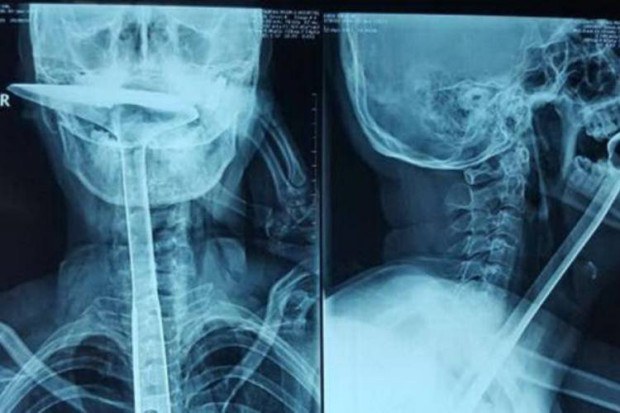

สาวจีนวัย 31 ปีที่อยู่ที่เมืองตงก่วน มณฑลกวางตุ้งของจีน ถูกหามส่งโรงพยายาลโดยมีตะหลิวทำกับข้าว ความยาว 30 ซม. เส้นผ่าศูนย์กลาง 2.5 ซม. ติดอยู่ในลำคอ หลังเจ้าตัวมีความรู้สึกเหมือนมีอะไรติดอยู่ในลำคอทำให้หายใจไม่สะดวก เธอเลยเริ่มด้วยการใช้นิ้วมือล้วงไปในคอแต่ก็ไม่ดีขึ้น จึงเปลี่ยนเป็นตะเกียบ 3 อัน ซึ่งก็ไม่ดีขึ้นอีก คราวนี้เลยใช้ด้ามตะหลิวอะลูมิเนียมล้วงลงไปในคอตนเองหวังเคลียล์พื้นที่ให้โล่ง แต่ดันพลาดเอาออกมาไม่ได้ โชคดีลูกสาววัย 4 ขวบเห็นเหตุการณ์ ตะโกนร้องขอความช่วยเหลือ จนถูกนำตัวส่งโรงพยาบาลในที่สุด

ทีมแพทย์ต้องทำการผ่าตัดเพื่อนำตะหลิวอันดังกล่าวออกมาจากหลอดอาหารของเธอ ซึ่งประสบความสำเร็จด้วยดี แต่หลอดอาหารของเธอเสียก็หายไปกว่า 80 % แพทย์จำเป็นต้องผ่าตัดเอาหลอดอาหารออกไปถึง 20 ซม. จากทั้งหมด 25 ซม. และยืดกระเพาะอาหารขึ้นมาเพื่อเชื่อมต่อกับหลอดอาหารส่วนที่เหลือ เพื่อให้เธอรับประทานอาหารได้เป็นปกติ ซึ่งแพทย์ยังกล่าวอีกว่า ไม่พบสิ่งผิดปกติที่จะทำให้ผู้ป่วยหายใจลำบากแต่อย่างใด นอกเหนือไปจากด้ามตะหลิวอันนั้น คาดว่าเป็นการคิดไปเองมากกว่า